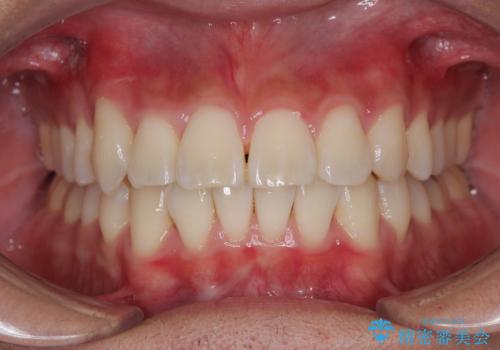

- 前歯の出っ歯と口元の閉じにくさを気にして来院された患者様です。

口元を積極的に引っ込めるために、上下左右の小臼歯4本を抜歯することとしました。

4本の歯を抜歯したことで、飛び出していた口元が引っ込み、横顔が大きく改善されました。